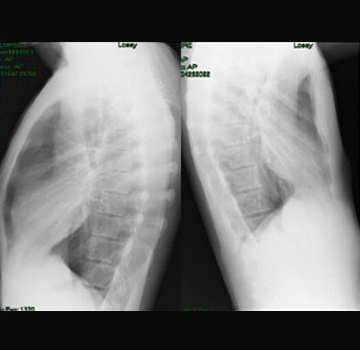

Pektus Arkuatum

Pektus Arkuatum (Mikst Deformite)

Pektus ekskavatum sternum ve kıkırdak kostaların değişik derecelerde depresyonu ile karakterize ...